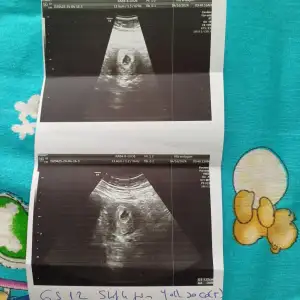

Benimde aşırı kanamam olunca acile gitmiştim ordaki aferdersiniz gerizekalı bana kesesi bozulmuş gibi sagliksizdir bu düşük yaparsın dedi beni kahretti o gece sabaha kadar uyumadım sabah direk özel prof gittim kesesi gayet normal dedi aynen senin gibi 5+4 galiba bak ultrason resmini de aticam

Hayir özele gittim cnm bak bu benim kese senin daha duz duruyo sanki baksana

Bak canım bana gittiğim özel prof dedi bu ultrason cihazını hareket ettirdikce onun görüntüsü değişir benim sonraki ultrason resmim yamuk yumuk birşey sen bol bol su iç dinlen bak bebeğin görünmüş bebeğe genetik pgt yapıldı mı

Bak nasıl yamuk duruyor ama hareket ettirdiği için ultrasonda ben görmüştüm mesela yuvarlakti burda bir tuhaf bebeklerim